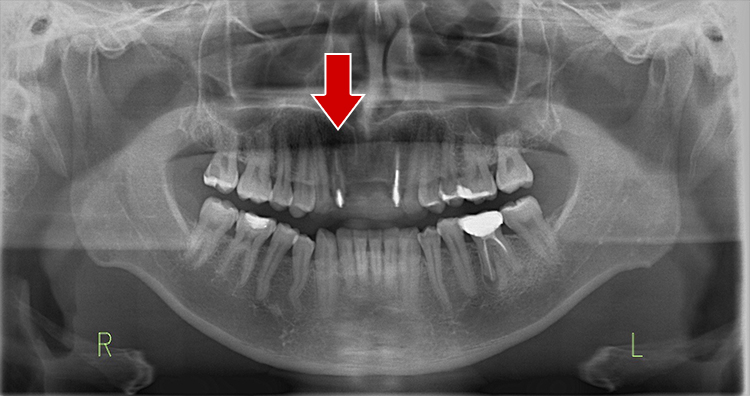

超最難関case(根尖病巣+パーフォレーション(術者のミス)

通常は「抜歯が当然」のcaseですが抜歯なしで治療成功事例

右下の画像が一番変化を診る上で基準となる画像でして(CT)、根の先端の病気が減っていること、白く濃く映った根のお薬がしっかりと入っている事が分かると思います。根の途中の黒い穴は、最初のドクターが謝って穴をあけてし合った後です。こういった高度な治療もセカンドオピニオンとしてお受けしております。

治療前

治療中

治療1年後

治療後3年後

レントゲンで施術前と施術後の比較

・赤色の部分→ドクターのミスをした箇所になります「パーフォレーション」

→結果、、、そこから病気ができています。。。

→通常はこれだけで「抜歯」となります。。。

・黄色の部分が根尖の病巣です。

→この原因でも抜歯となることもあります。

こちらの症例に関しても抜歯するくこともなく、治療成功となります。